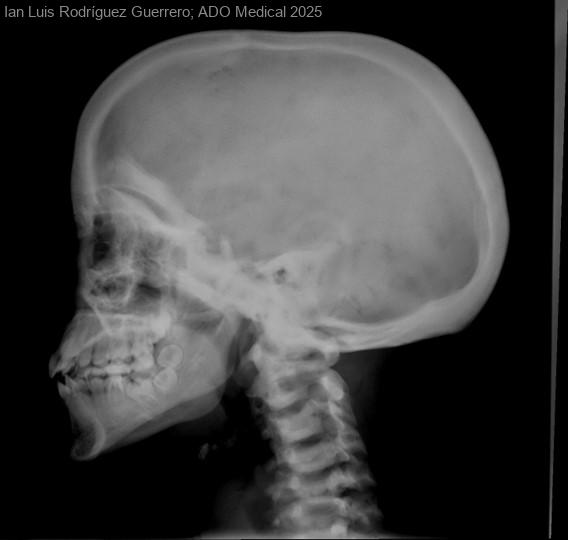

Paciente mujer de 15 años, con antecedentes de presenta fracturas patológicas y de luxación de rótula. En diciembre de 2022, sufrió un traumatismo leve en la mano derecha, con posterior fractura en la diáfisis del...